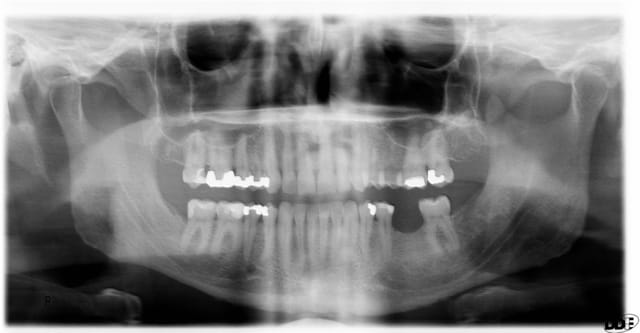

Contrôle post-op 2 ans.... reformation osseuse....

des hypothèses, pour tenter de comprendre (en plus du talent du praticien) ?

Hygiène extrême ? Prédisposition congénitale ? Marque de l'implant

la nature a toujours tendance a aplanir ses courbes!